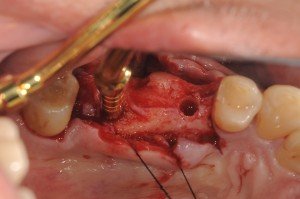

このケースは、上顎5,7番部位へ2本のストローマンティッシュレベルインプラントをソケットリフトで埋入しました。

5番部位の洞底の皮質骨が固くオステオトームのみでは、若木骨折できなかったので、ピエゾサージェリーを用いました。

7番部位は、スムーズにオステオトームテクニックでソケットリフトできました。